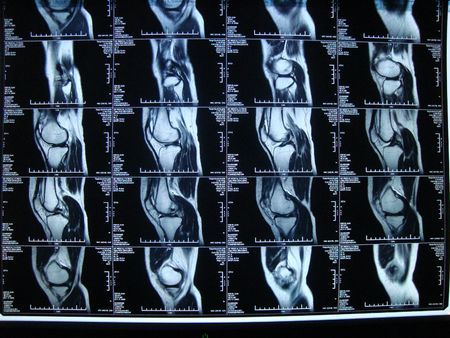

正常膝盖核磁共振

正常膝盖核磁共振,膝盖核磁共振

这是我母亲膝盖的核磁共振片子, 求医生帮忙鉴定一下伤势.

【关节影像】膝关节的磁共振(mri)解剖表现

膝关节半月板病变的核磁共振检查的诊断与鉴别

膝关节核磁共振ppt

膝关节的核磁片子,半月板有损伤,自己也看不太懂,帮我

膝盖核磁共振

膝盖核磁共振片子

膝盖核磁共振报告

膝盖核磁共振图片

膝盖核磁共振片子图解